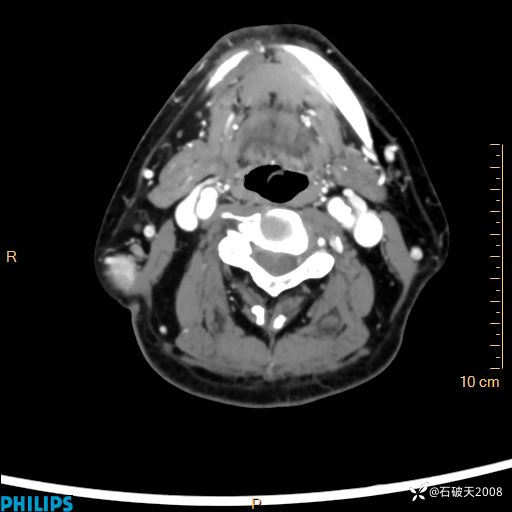

病例分享:颈部占位,一周后公布病理

男 57岁 主 诉:发现右侧颌下肿物1月余。

现病史:1月余前家属发现右侧颌下肿物。局部皮肤无红肿、热痛,无吞咽困难,无异物感,无恶心、呕吐,无头痛、头晕,无胸闷、胸痛,无发热、咳嗽、咳痰及呼吸困难。于我院行体表肿块彩超检查(2024.03.15我院)示:右侧耳下皮下软组织内低回声,未治疗。今为进一步治疗门诊以“腮腺肿瘤”为诊断收住我科,发病来患者神志清,精神可,饮食、睡眠及大小便正常,体重无明显下降。

静脉期